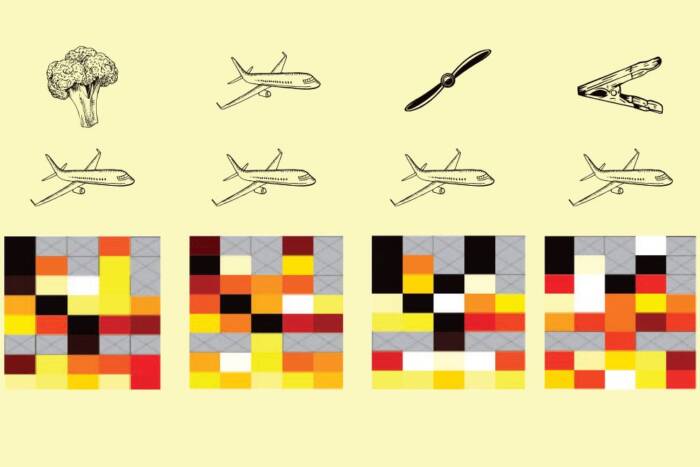

First molecular glimpse: Molecular markers delineate the different cell types within an attached human embryo, shown here 12 days after fertilization. A structure called the epiblast, for example, is shown in green. The key developmental landmarks observed using this novel system accurately match those of normal human development, up to 12 days after fertilization.